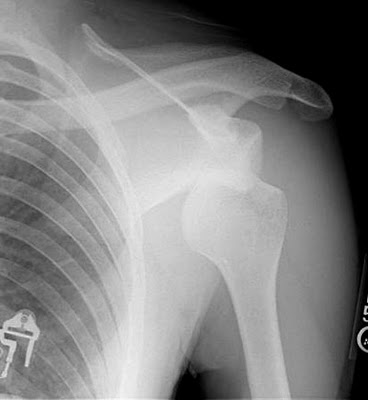

Well, we all know that “the word” travels fast in the fire department and apparently I’m a hot topic for the rumor mill once again so lets set the record straight. I was injured last week. A dislocated shoulder early Monday morning.  NO… it was NOT a football injury. NO… it was not from a bar room fight. YES.. a cow ran me over and YES… she was 10 times bigger and meaner than the one that damn near killed Lynn Flora (lol). There is/was good and bad news. The good news is that nothing was torn … the bad news is that its sore….REAL sore. I’m on the road to recovery though.. back to work today and planning on football practice tomorrow. A little black and blue, still sore but alive and kicking (I’m tougher than I look you know). The cow???? Well lets just say she probably hurt a little too…

NO… it was NOT a football injury. NO… it was not from a bar room fight. YES.. a cow ran me over and YES… she was 10 times bigger and meaner than the one that damn near killed Lynn Flora (lol). There is/was good and bad news. The good news is that nothing was torn … the bad news is that its sore….REAL sore. I’m on the road to recovery though.. back to work today and planning on football practice tomorrow. A little black and blue, still sore but alive and kicking (I’m tougher than I look you know). The cow???? Well lets just say she probably hurt a little too…  This is not the first time that me and a farm animal have squared off. A few years back, a colt and I had a little misunderstanding and the firehouse cartoons were funny as crap! It used to be posted on the Rumor Mill but I can’t seem to get it to load. I will work on that and get it up here so you all can have something else to laugh at me about… I am here for your entertainment you know..(LOL). Seems my last post drew a few comments and I’ll say this… comments are welcome.. good or bad. Hey, I know I’m a target for some and not the most popular for others. The thing is, if you don’t like what I’m posting on or could care less what I have to say on this or that… DON’T READ THIS BLOG. Easy huh? The title “Wooden Ladders and Iron Firemen” was meant to show respect to the men who fueled my desire and Passion for this job. The men who were tougher than the equipment they had (or equipment they didn’t have). The title in no way was a representation of how I view myself but I will say that I have had the honor to go through a few doors with some “iron firemen” and it seems more and more today that the title has been reversed. Today, it’s more like Iron ladders and wooden firemen. Now that’s not to say that we don’t have some good ones left because we do but a lot has changed. One of my favorite reads is Fire Engineering Magazine. If you don’t take this mag you should really consider doing so. You can check them out online as well. Anyway, the March issue has a good article Firefighter Casualties: when “old school firefighting” doesn’t work. Look it up on page 105. Another good read from their web site is “The new old school“. Just today, Battalion Chief Bobby Slayton stopped in for a visit. He literally sat for hours at the kitchen table telling us stories of the “good ol days”. He had us rolling in the floor! I hope the boys know how lucky they are to have had the chance to sit there and hear Bobby be so open and candid with his stories.